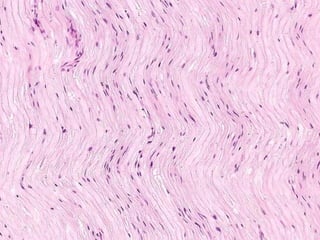

• #4 LONGITUDINAL H&E section of a peripheral myelinated nerve. Does the word “wavy” come to mind? Wavy Wavy Wavy Wavy Wavy Wavy Wavy Wavy Wavy Wavy Wavy Wavy Wavy Wavy Wavy Wavy Wavy Wavy Wavy Wavy Wavy Wavy Wavy Wavy Wavy Wavy Wavy Wavy Wavy Wavy Wavy Wavy Wavy Wavy Wavy Wavy Wavy Wavy Wavy Wavy Wavy Wavy Wavy Wavy Wavy Wavy Wavy Wavy Wavy Wavy Wavy Wavy Wavy Wavy Wavy Wavy Wavy Wavy Wavy Wavy Wavy Wavy Wavy Wavy Wavy Wavy Wavy Wavy Wavy Wavy Wavy Wavy Wavy Wavy Wavy Wavy Wavy Wavy Wavy Wavy Wavy Wavy Wavy Wavy Wavy Wavy Wavy Wavy Wavy Wavy Wavy Wavy Wavy Wavy Wavy Wavy Wavy Wavy Wavy Wavy Wavy Wavy Wavy Wavy Wavy Wavy Wavy Wavy Wavy Wavy

• #12 The more longitudinally a nerve happens to be sectioned, the more “wavy” it appears.